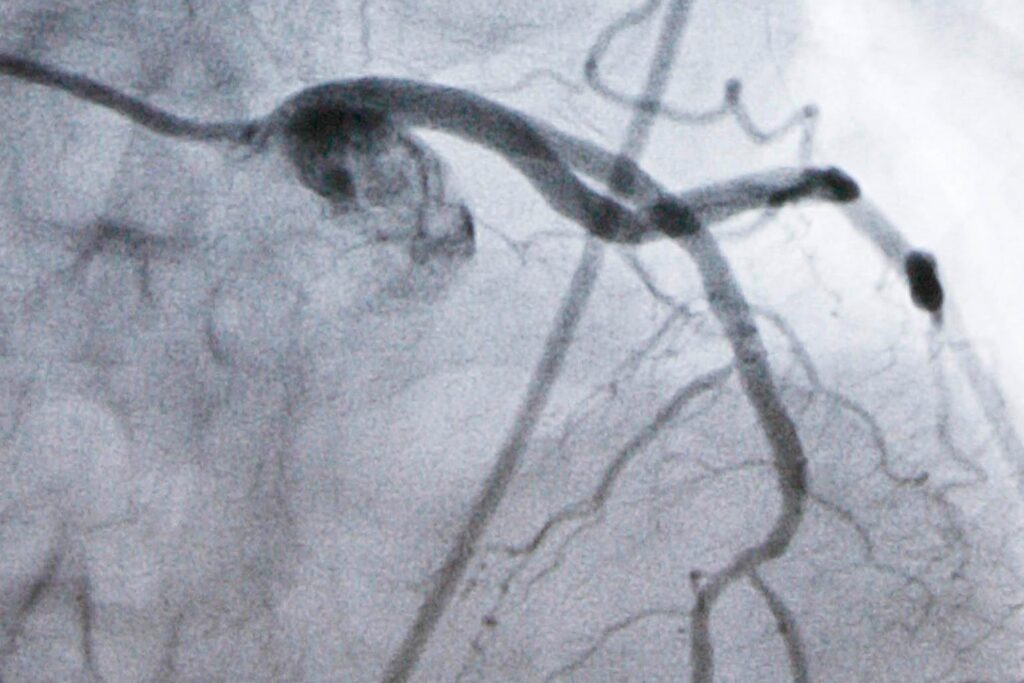

Heart disease is the nation’s leading cause of death and high LDL cholesterol, which causes plaque to build up in arteries, is a top risk factor for heart attacks and strokes. While an LDL level of 100 is considered fine for healthy people, doctors recommend lowering it to at least 70 once people develop high cholesterol or heart disease — and even lower for those at very high risk.